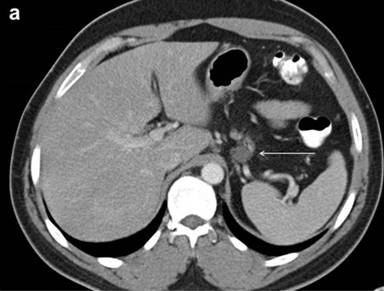

A 35-year-old man presented to the emergency department with complaints of abdominal and back pain after a fall. On axial imaging, a cystic neoplasm of the pancreas was incidentally discovered. The CT scan revealed a 2.1x1.7 cm, well-defined, low-density, non-calcified cystic lesion arising from the pancreatic tail (Figure 1a). The differential diagnosis included pseudocyst, mucinous or serous pancreatic cyst, and malignant pancreatic cyst. The serum tumor markers included normal CEA and CA 19-9; chromogranin A was elevated at 237 ng/mL (reference range: 0-95 ng/mL) and neuron specific enolase was also elevated at 14.2 µg/L (reference range: 3.7-8.9 µg/L). MRI and 18F-FDG-PET were not utilized.

The patient underwent EUS and FNA to further characterize the cyst and guide management recommendations. EUS described an irregular, heterogeneous, complex cyst-like lesion at the tail of pancreas. The cyst did not appear to communicate with the main pancreatic duct and the main pancreatic duct appeared normal. Multiple septations and hypoechoic debris gave a complex cyst appearance (Figure 1b). FNA using a 22 gauge needle retrieved a whitish, necrotic appearing material. CEA and amylase levels could not be determined because no fluid was returned. Cytology of the FNA specimen identified histiocytes, benign epithelial cells and lymphocytes.

Figure 1. a. CT image of pancreatic dermoid cyst (white arrow) demonstrating a well-circumscribed, hypodense lesion. b. EUS revealed a complex cyst (white arrow) in the tail of the pancreas. |